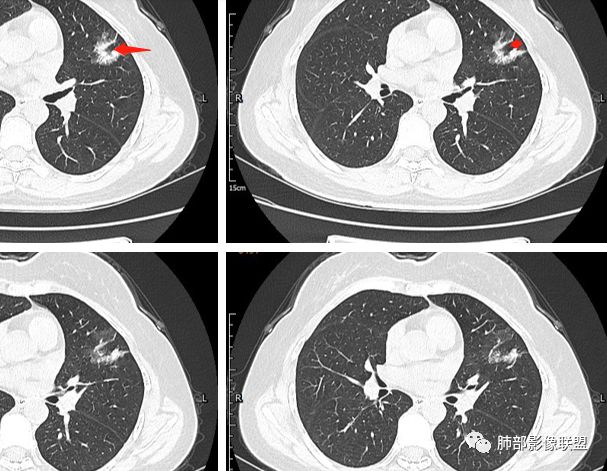

二.关于胸膜下小结节:

结节影太小,尚未能够充分反映出影像学特征。随访观察应当是恰当的处置方式。

这有一个小结节